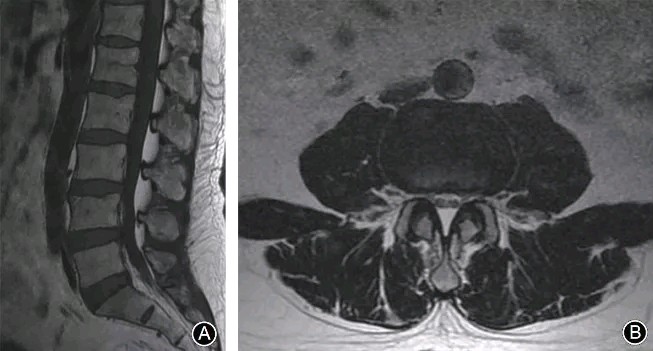

患者,女,76岁,腰腿疼多年伴偶发神经源性跛行

A:MRI矢状位示腰椎体上缘至腰4/5椎间盘区间,可见腰椎管多节段狭窄及椎管内马尾神经迂曲冗长

B:MRI轴位示增粗的马尾神经在狭窄内的异常分布排列